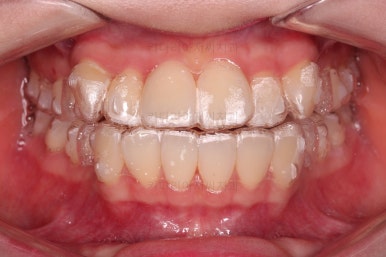

인비절라인을 착용한 모습인데요.

필요한 치아는 발치가 되어 있고요.

눈에는 잘 띄지 않지만 치아 색깔나는 재료로 어태치먼트라고 하는 부착물도 부착되어 있어요. 장치를 잘 잡아주는 손잡이와 같은 역할을 해줍니다.

장치 장착 후 얼굴모습 참고해 주세요.

치아만 있을 때랑은 약간의 이질감이 느껴지긴 하지만, 브라켓-철사교정만 하겠습니까 ^^